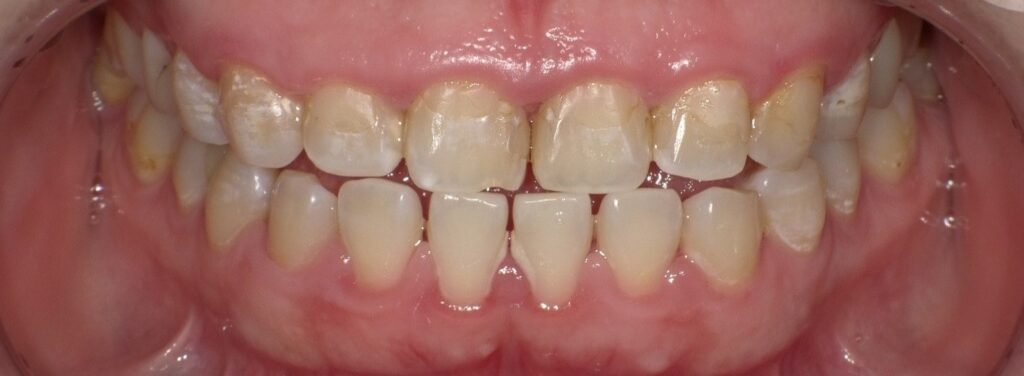

初回実施前の口腔内です。

普段ジャスミン茶をよく飲むそうです。ジャスミン茶にはタンニンが含まれており、着色の原因になります。(コーヒー・紅茶や緑茶に比べたら少なめです。)